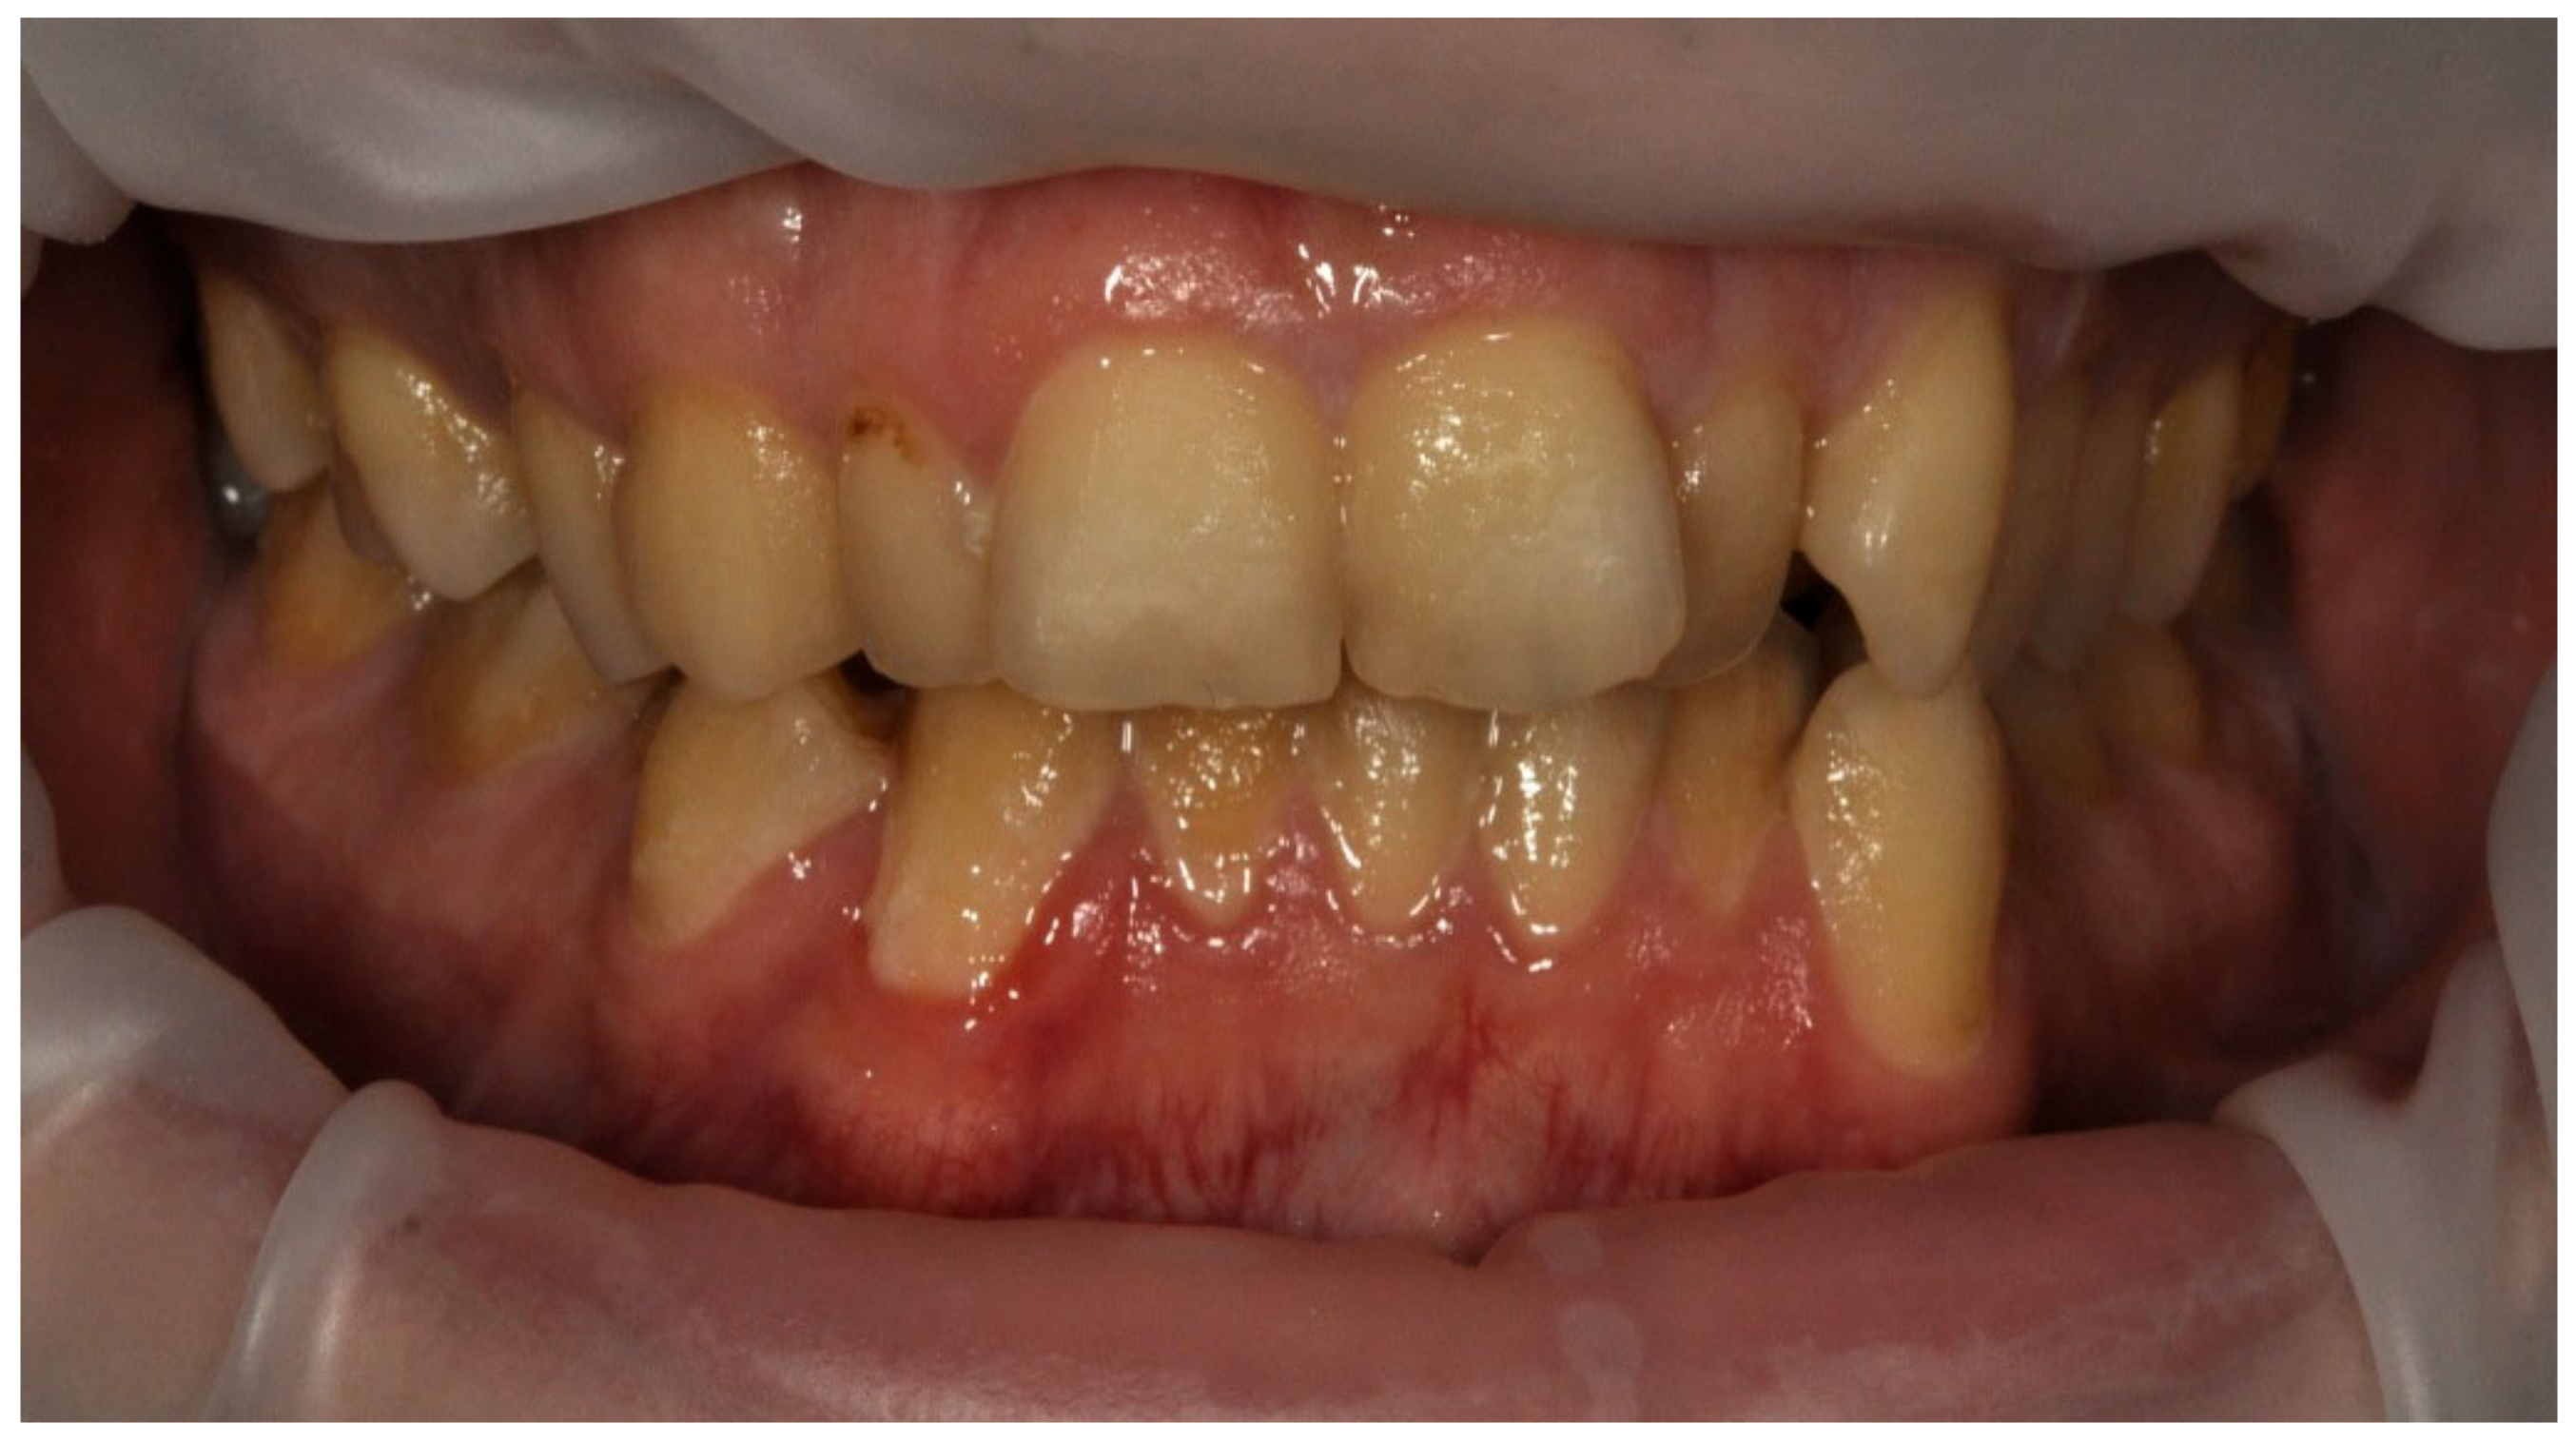

All p > 0.05, so the study and control groups did not differ significantly in terms of the value of the DMF index or any of its components. It is noteworthy that on average in the study and control group, the patients had more than four caries-related defects and at least one tooth was removed. The patient’s clinical situation with a very high DMF value is shown in Figure 5.

Examples of erosive defects occurring in the examined patients are presented in Figure 6, Figure 7a,b and Figure 8a–c.

Figure 5. Man, 52 y.o. Clinical situation presenting very high DMF value.

Figure 7. (a,b) Man, 33 y.o. Advanced internal and external erosion. The patient reported regular vomiting and consumption of approximately 6 L of Coca-Cola per day over a period of more than 6 months—front teeth and upper arch.

Ijerph 20 04792 g007aIjerph 20 04792 g007b

Figure 8. (ac) Woman, 29 y.o. Patient with advanced erosion and tooth wear—front view and upper and lower arches.

Ijerph 20 04792 g008